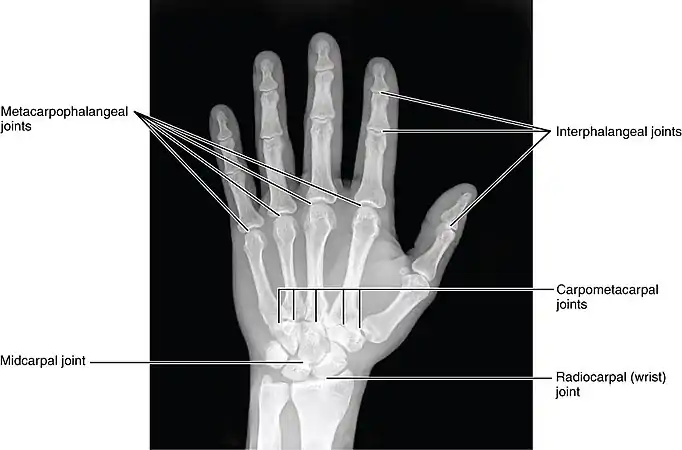

The interphalangeal joints of the hand are the hinge joints between the phalanges of the fingers that provide flexion towards the palm of the hand.

There are two sets in each finger (except in the thumb, which has only one joint):

- "proximal interphalangeal joints" (PIJ or PIP), those between the first (also called proximal) and second (intermediate) phalanges

- "distal interphalangeal joints" (DIJ or DIP), those between the second (intermediate) and third (distal) phalanges